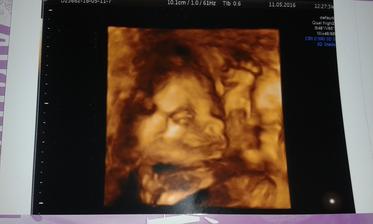

Klokan přiletí v září

autor@digklariska ja to davala dle filmu Jak dostat tatinka do polepsovny... mala je taky takovy maly Vasek 😉...